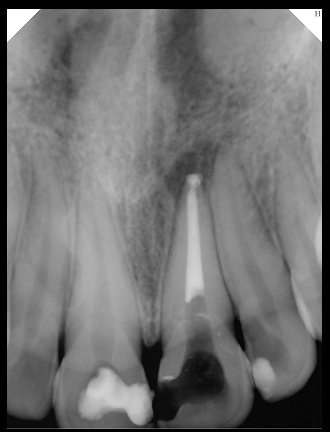

CR/DR 牙齿分割阶段记录

当前进展

- 完成了 CR/DR 牙齿相关分割训练

- 当前结果已经达到阶段预期,但仍有细节问题需要继续处理

相关测试

遇到的问题

- 训练过程中出现过 mask 下移问题

- 部分结果会出现 box 填充异常

- mask 边缘仍然有比较明显的锯齿感

参考

第二版算法问题测试

Updated: 2026-04-13(更新日期)

| 第一版 | 第二版 | 是否解决 | |

|---|---|---|---|

![]() | ![]() ![]() 边角识别有问题 龋齿识别不全 牙髓识别不全 | ![]() | 解决 |

![]() | ![]() 边角识别有问题 识别信息有误 自查(牙冠识别不全) | ![]() | 解决 |

![]() | ![]() ![]() 边角识别有误 大范围填充识别遗漏 | ![]() | 解决 |

![]() | ![]() 识别信息不全 | ![]() | 解决 |

![]() | ![]() ![]() 边角问题 牙胶识别不全 牙冠识别不全 | ![]() | 解决 |

![]() 换图片 | ![]() | ![]() 牙冠部分稍微白了一些就识别成小范围修补,部分判断异常 | 部分解决,修复类略敏感,牙冠部分稍微白了一些就识别成小范围修补,部分判断异常。 |

![]() | ![]() ![]() 牙冠识别不全 牙髓不全 根尖炎龋齿识别有误 | ![]() | 解决 |

![]() | ![]() | ![]() | 解决 |

![]() 换图片 | ![]() | ![]() | 解决 |

![]() | ![]() 牙冠识别有误 | ![]() | 解决 |

![]() 换图片 | ![]() ![]() 边角识别有误 | ![]() 修复类敏感 | 部分解决,图像过白,导致修复类判断异常。 |

![]() 换图片 | ![]() 牙冠识别不全 | ![]() 修复类敏感 | 部分解决,图像过白,导致修复类判断异常 |

结论:修复类出现了不鲁棒的情况,后续需要加入轮廓的扩充数据进行增强。